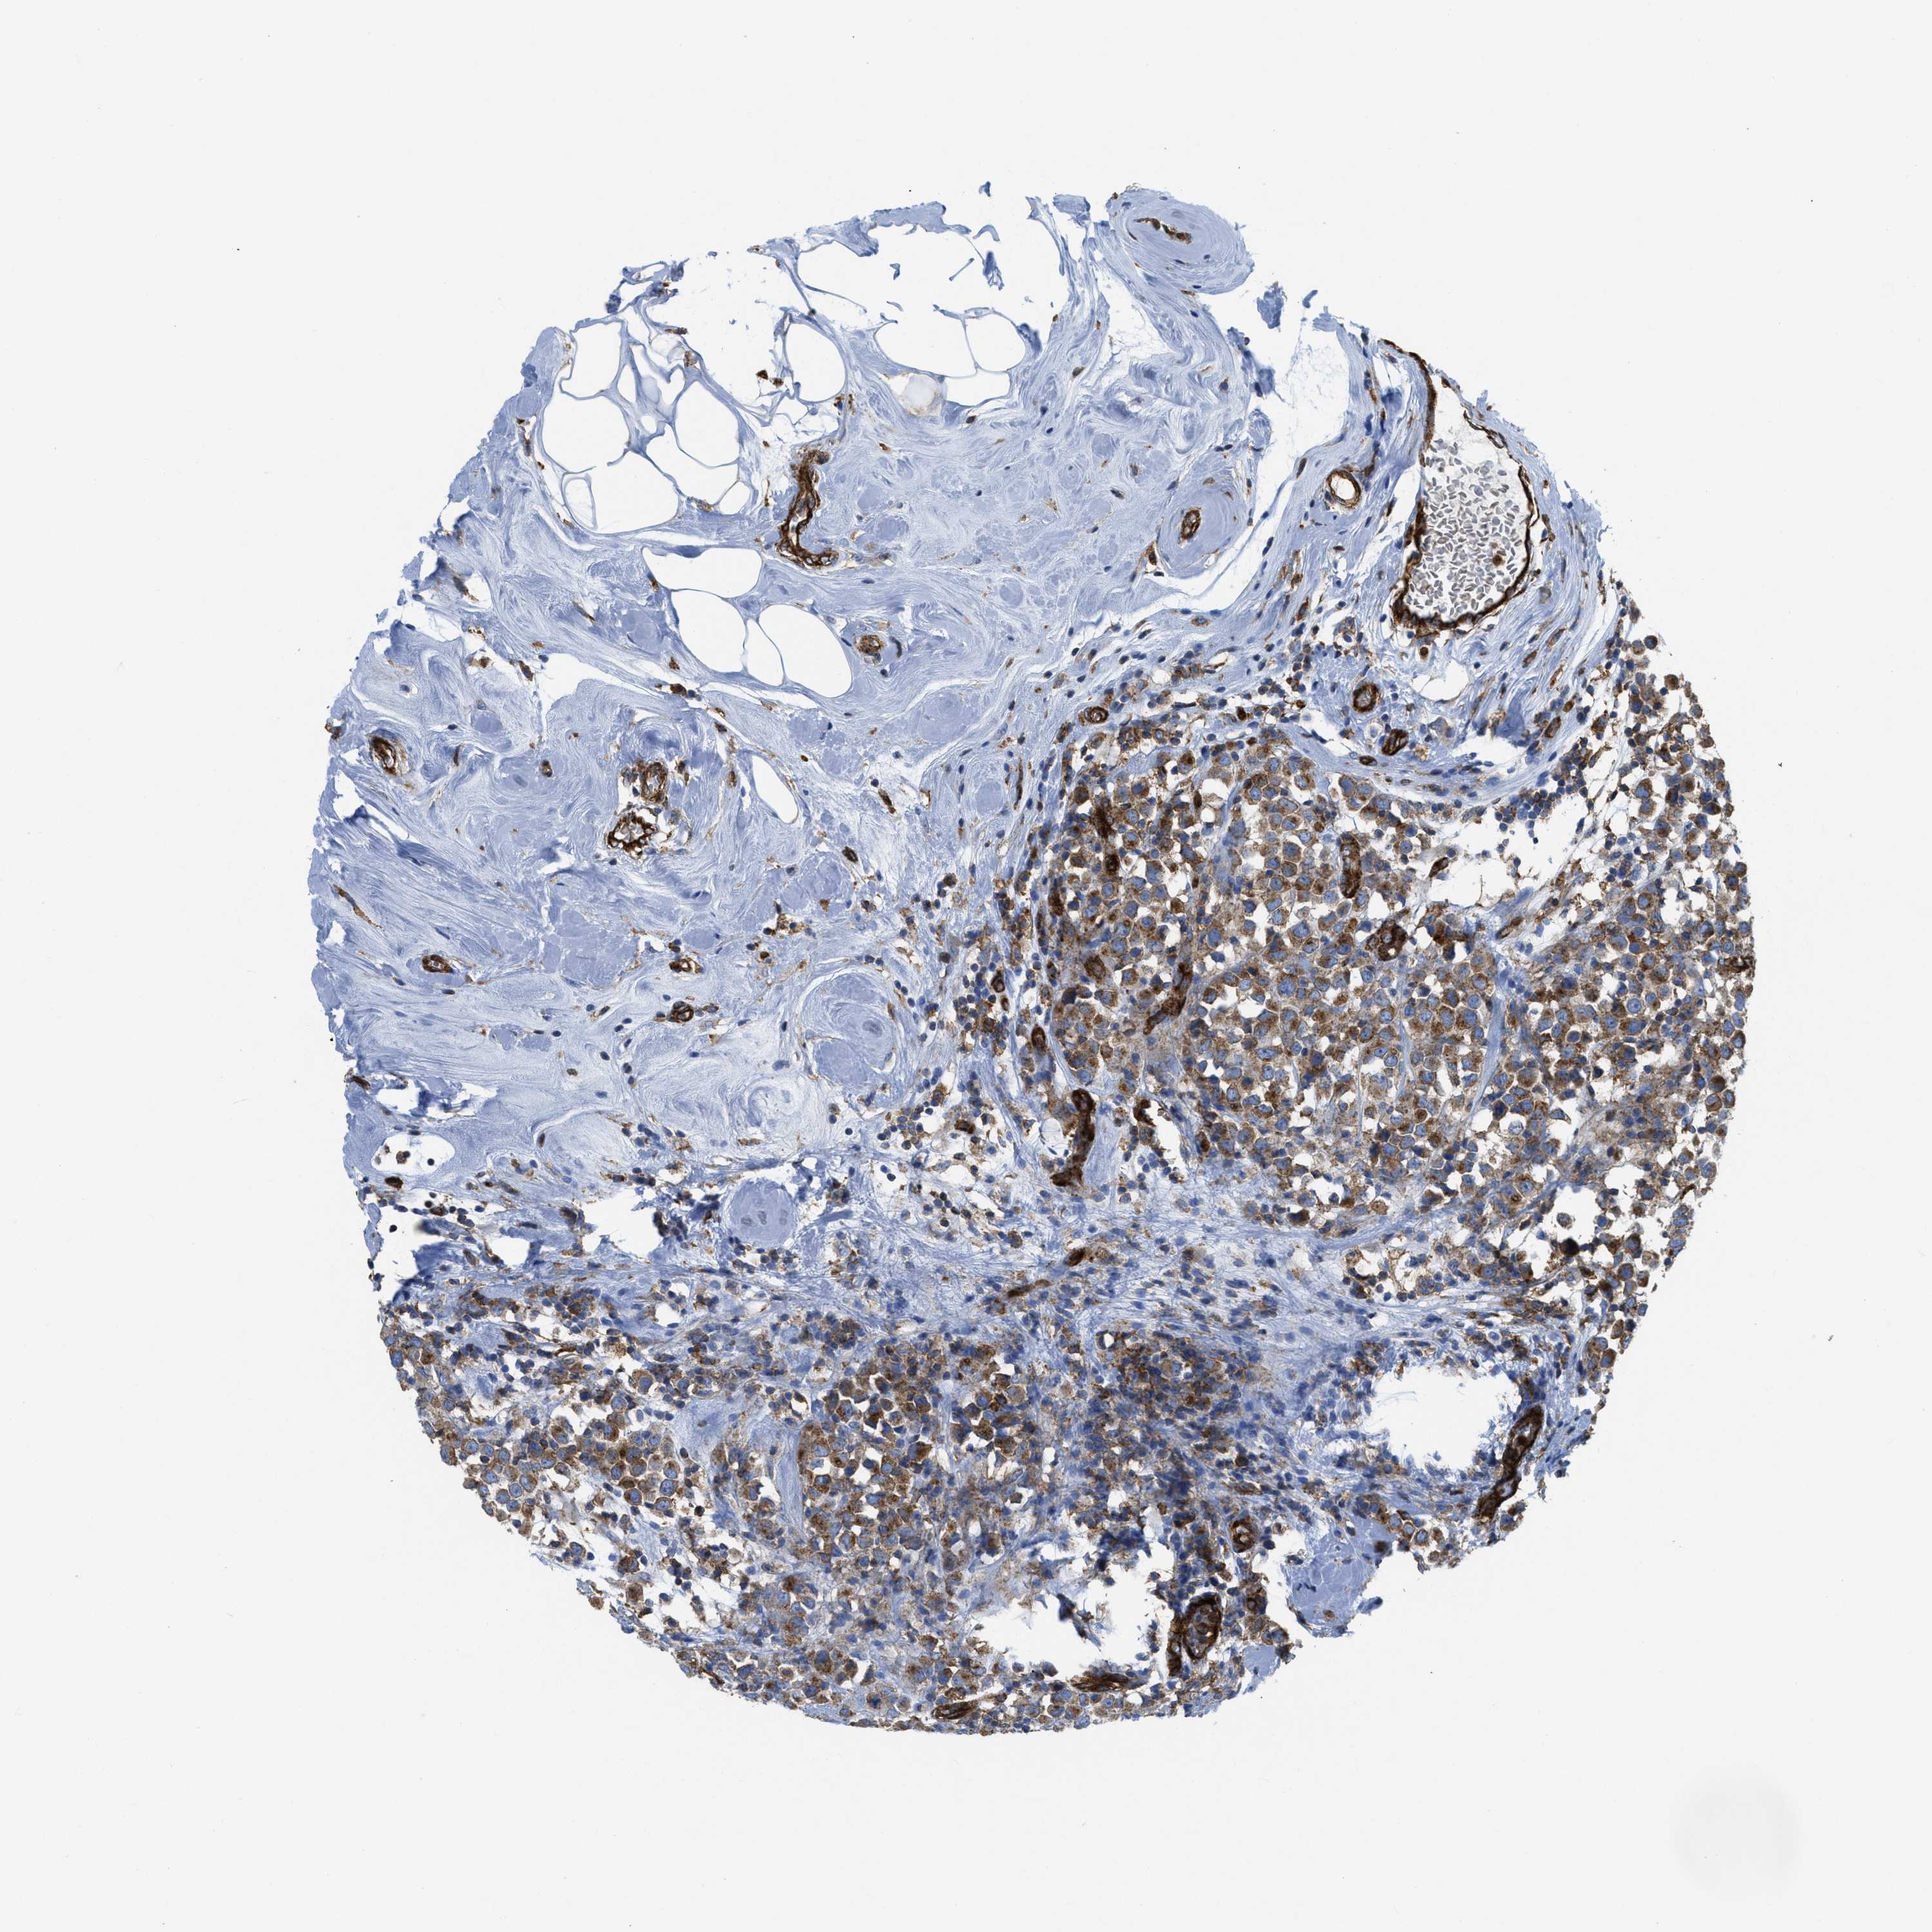

CANCER BREAST CANCER Show tissue menu

BRCA TCGA BRCA VALIDATION PROTEIN EXPRESSION